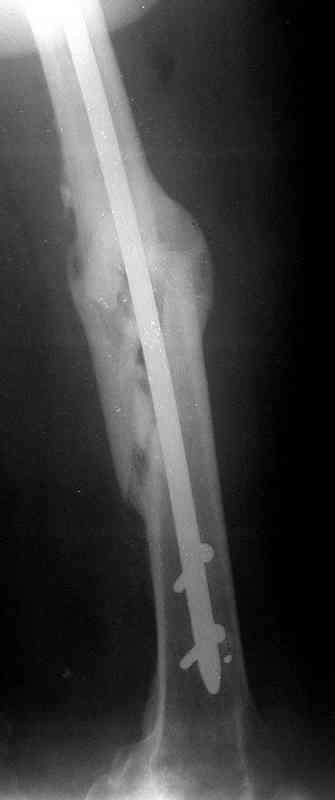

месяцев дистракции укорочение левого бедра удалось полностью устранить. 22.02.00, т.е. через 2 месяца после повторного остеосинтеза, больному произведено дистальное блокирование штифта двумя винтами и демонтирован аппарат Илизарова. В течение 2 недель после операции больной ходил с помощью костылей, потом 2 недели с тростью. Опороспособность и функция оперированной конечности полностью восстановились через 4 недели после операции.

Фиксаторы удалены через 12 месяцев после операции, выполненной по поводу замедленной консолидации перелома бедра с его укорочением.

Спасибо! Истинно мастерская работа. Представляю как счастлив пациент исходом этой истории.

На финальных снимках видно - сращение прям таки железное. Если Вы не устали отвечать, осмелюсь задать еще вопрос - что-то принимал пациент в целях ускорения сроста (кальций, режим питания). Интересны также вопросы восстановления функций конечности - в какой период были рекомендованы группы упражнений для восстановления основных групп мышц?